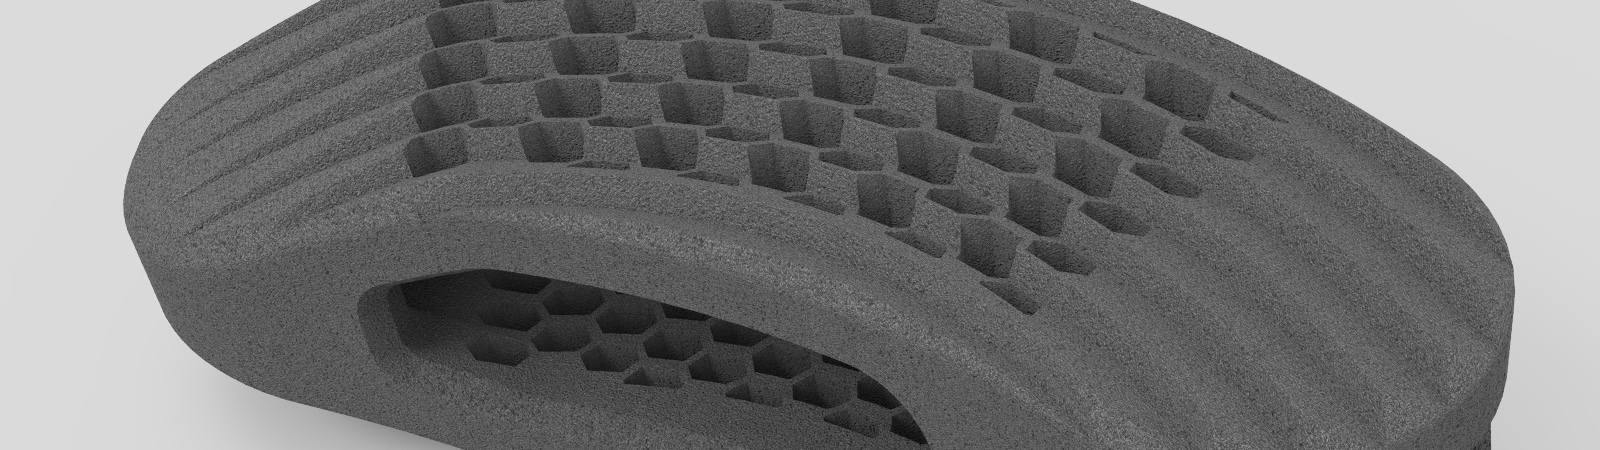

zurückUNI-LOCC-SLMOblique-Cage aus Titan

Uni-LOCC bedeutet »Unilateraler Offset Contact Cage«. Der Name steht durch seine spezielle Kurvierung für eine optimale laterale Abstützung. Verlängert um einige Millimeter, wird die Last beim schrägen Einbringen auf den gesamten Wirbelkörper optimale verteilt.